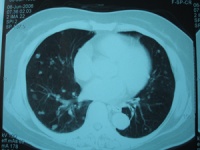

4.CT检查示肾内实质性占位性病变及CT值低的脂肪成份。

cm,病程1个月~7年。主要临床症状为腰部不适、胀痛、包块、出血性休克等。22例均行KUB加IVP和CT检查,2例行MRI检查。IVP表现为正常或提示肾盂肾盏受压变形;B超检查多表现为强回声光团,也表现为混合回声,诊断准确率为86.4%(19/22);CT平扫多表现为圆形或类圆形低密度或极低密度病灶,病灶位于肾实质内或突出于肾轮廓外,诊断准确率为90.9%(20/22)。

的良性肿瘤,由于肾基质缺乏脂肪和平滑肌,故通常认为属错构瘤。有20%肾错构瘤合并节结性硬化症,并双侧同时发生,病变较小,常并发癫痫、智力低下、面部皮脂腺瘤等。肾错构瘤以中年女性为多见。陈承志等报告男女比例为1∶2.25,本组为1∶1.2。 B超结合CT诊断肾错构瘤有重要价值,随着超声、CT和MRI的应用,肾错构瘤的发病率有所增加,术前诊断准确率也有所提高。肾错构瘤与肾细胞癌影像学鉴别要点在于肾错构瘤含有较多脂肪成分而正常肾及肾细胞癌组织极少或没有,肾错构瘤在B超图像中表现为强回声光团,偶然可见混合性低回声。CT显示比超声图像更敏感,CT值于小-10Hu,因此,典型的肾错构瘤不难诊断。MRI检查时,T1加权像较低,T2加权像又极高。IVU主要了解双肾功能情况,对于评估肾功能不良患者是否进行手术以及手术方式的选择具有重要作用。